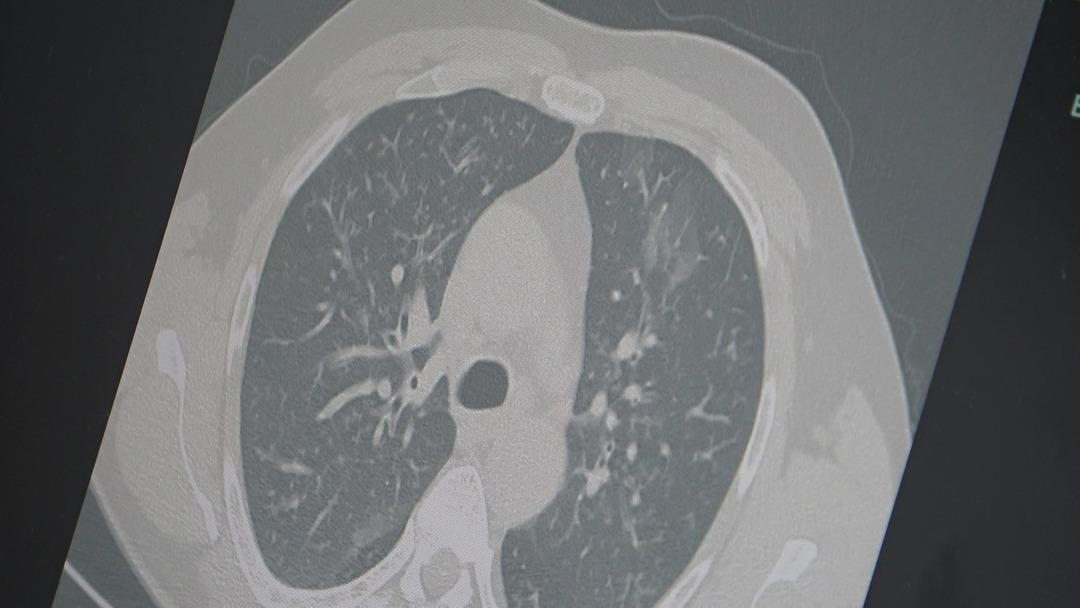

Dr. Özkaya emphasized that flu and COVID-19 carry the risk of turning into pneumonia, saying, "In many of our patients, the disease progresses to the lungs after flu or COVID-19 and presents as pneumonia. We are also observing an increase in the number of hospitalized patients."

"We recommend that our citizens with even the slightest flu-like symptoms rest at home. Those experiencing a prolonged cough and shortness of breath should definitely consult a doctor, get a chest X-ray, and receive appropriate treatment." Source: İHA